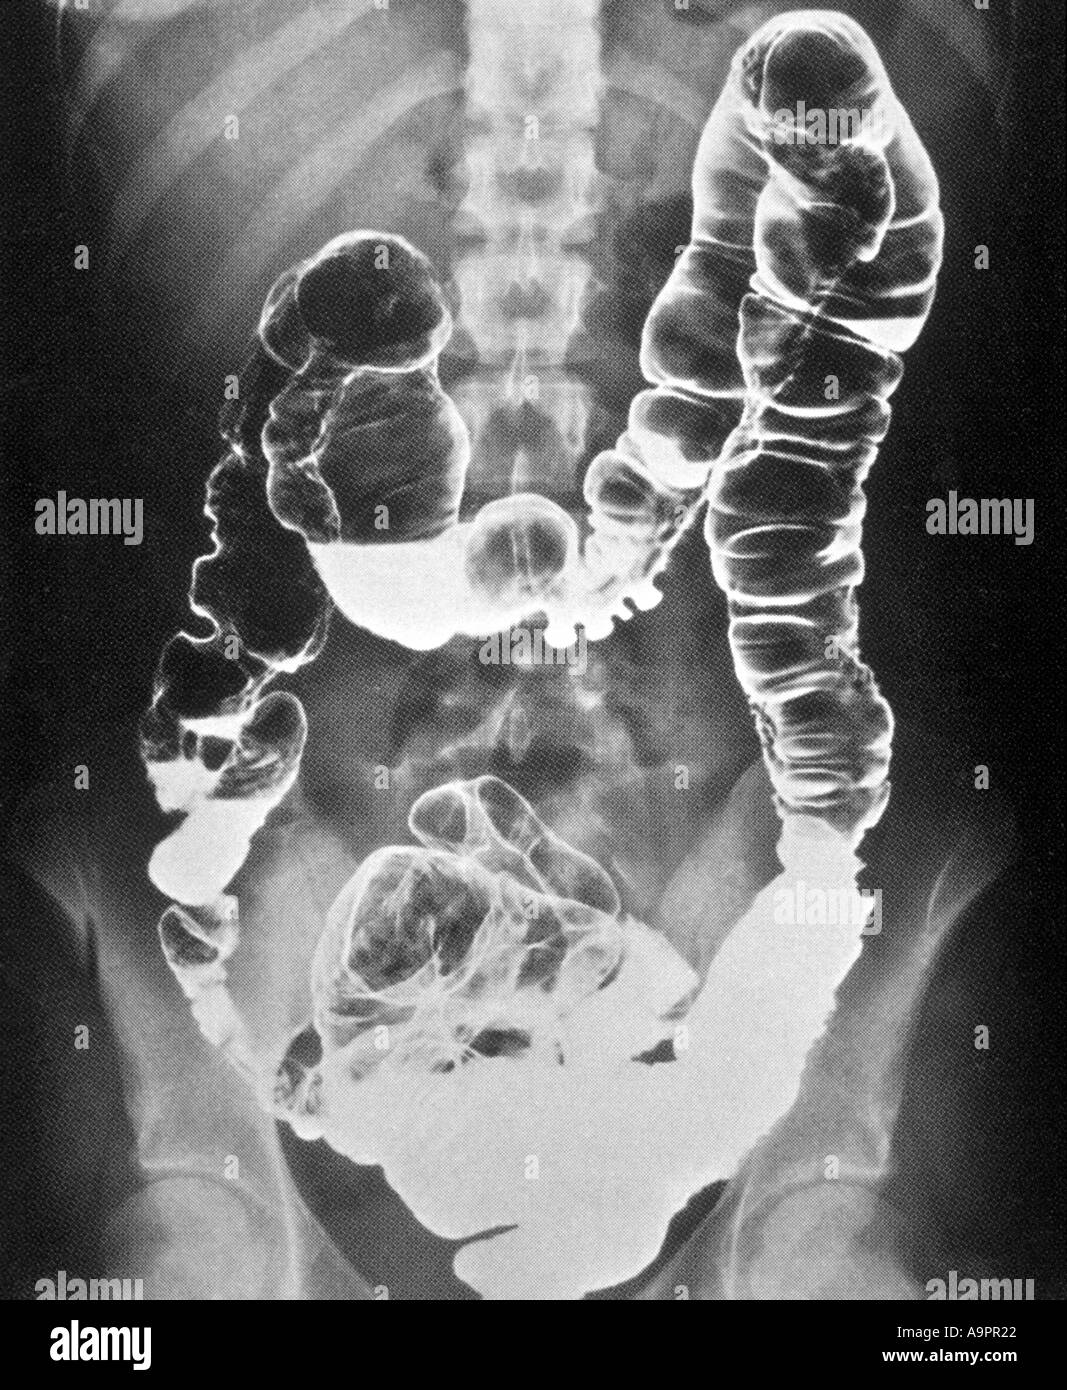

Crohns Disease Xray

Crohn's disease | Radiology Case | Radiopaedia.org Crohn's Disease Radiology: CT, MRI, Ultrasound, and More LearningRadiology - Crohn Disease, Regional Enteritis Crohn disease - X-ray: MedlinePlus Medical Encyclopedia Image | Crohns Disease Xray